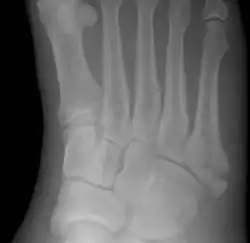

Jones fracture as seen on Xray

A Jones fracture is a broken bone in a specific part of the fifth metatarsal of the foot between the base and middle part .[8] In general, fifth metatarsal fractures heal readily, but a Jones fracture must be recognized and accurately diagnosed because of its higher rate of delayed healing or nonunion.[4] It results in pain near the midportion of the foot on the outside.[2] There may also be bruising and difficulty walking.[3] Onset is generally sudden.[4]

Diagnostic X-rays include anteroposterior, oblique, and lateral views and should be made with the foot in full flexion.